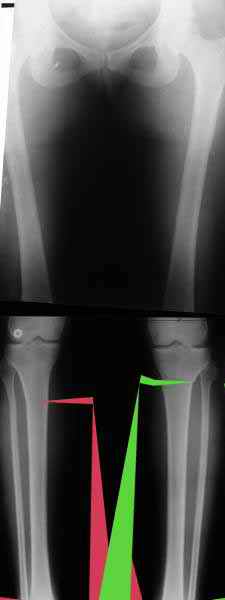

Вот, с учетом и без учета, и на разных уровнях...

AC> Вот, с учетом и без учета, и на разных уровнях...

Из приведнной схемы не совсеим понял что означают разноцветные линии.

И зачем латерализация периферического фрагмента. Я всегда делаю медиализацию. См схему. И для данного случая медиализация подходит как нельзя лучше.

a> Из приведнной схемы не совсеим понял что означают разноцветные линии.

Черные - это нынешняя механическая ось. Красные - это планируемая правильная ось.

a> И зачем латерализация периферического фрагмента.

;-) Читайте Палея. Стр. 114-115.

a> Я всегда делаю медиализацию. См схему. И для данного случая

Медиализация - это чисто эстетический прием, как я понимаю. Поскольку если делать остеотомию ниже вершины деформации, для восстановления оси надо делать смещение по ширине, в данном случае как раз латерализацию.

Мне представляется оптимальным на уровне 3-4 линии (т.е. как раз посредине отмеченной зоны). Если рассчимтываешь делать медиализацию, то параллельно суставной поверхности, иначе просто не сдвинешь без джистракции - отломки зацепятся. Если без медиализации - то вообще не имеет значения.